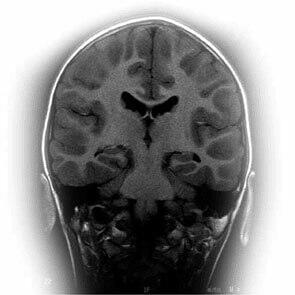

L'action de la pregnénolone sur la mémoire a été bien montrée aussi bien chez l'animal que chez l'homme. La pregnénolone est un antagoniste du GABA et un agoniste ou stimulateur des récepteurs NMDA (N-méthyl-D-aspartate) qui renforce le système des neuromédiateurs diminuant avec le vieillissement. La pregnénolone stimule également la synthèse de l'acétylcholine et ceci a été particulièrement bien démontré dans l'hippocampe.

Les actions de la pregnénolone

En revanche, les effets de la pregnénolone deviennent particulièrement intéressants pour la mémoire chez les personnes de plus de 50 ans. La pregnénolone est une des substances naturelles les plus actives pour stimuler et améliorer la mémoire chez l'animal. La pregnénolone bloque les effets inhibiteurs de l'acide aminé glycine et du GABA contribuant à l'équilibre de la balance inhibition / excitation du système nerveux central. Elle augmente le relargage de l'acétylcholine, puissant neuromédiateur, et agit sur les récepteurs NMDA (N-méthyl-D-aspartate) impliqués dans la mémoire.